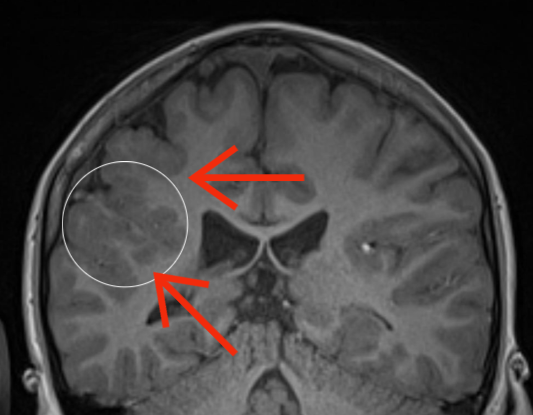

Polymicrogyria (PMG) is a cortical malformation characterized by irregular thickened grey matter in the cerebral cortex, with numerous small gyri, shallow sulci and loss of grey white matter differentiation (see Figure 1). Polymicrogyria is one of the most common malformations of cortical development and is most often related to genetic disorders although it can be caused by congenital viral infection [1]. PMG is a heterogeneous condition which can have variable distribution, extent, and severity [1]. Experienced neuroradiologists can accurately diagnose PMG using magnetic resonance imaging (MRI) but focal or more subtle PMG can be missed. Less experienced readers may not detect PMG with the same accuracy as it can be subtle, and computer aided diagnosis would be useful here.

Figure 1: Difference between PMG and normal brain on coronal T1 weighted MR images. The white circle on the first image shows thickened, irregular grey matter with numerous small gyri and shallow sulci, compared to normal grey matter in the white circle on the second image. The interface between cortical grey matter and white matter is irregular in PMG (red arrows on the first image) and smooth in normal brain (red arrows on the second image).